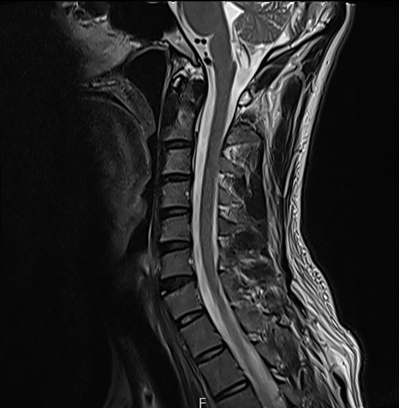

그림10.png 촬영 일시: 2025.04.13

<Fig 1. 목 MRI 영상>

검사 결과는 예상과 정확히 일치했습니다.

경추 2-3번 사이에 약간의 디스크 변성이 있었고,

이로 인해 후두신경이 압박받고 있는 상황이었습니다.

환자분께서 그동안 겪으신 모든 증상의 원인이

바로 여기에 있었던 것이죠.